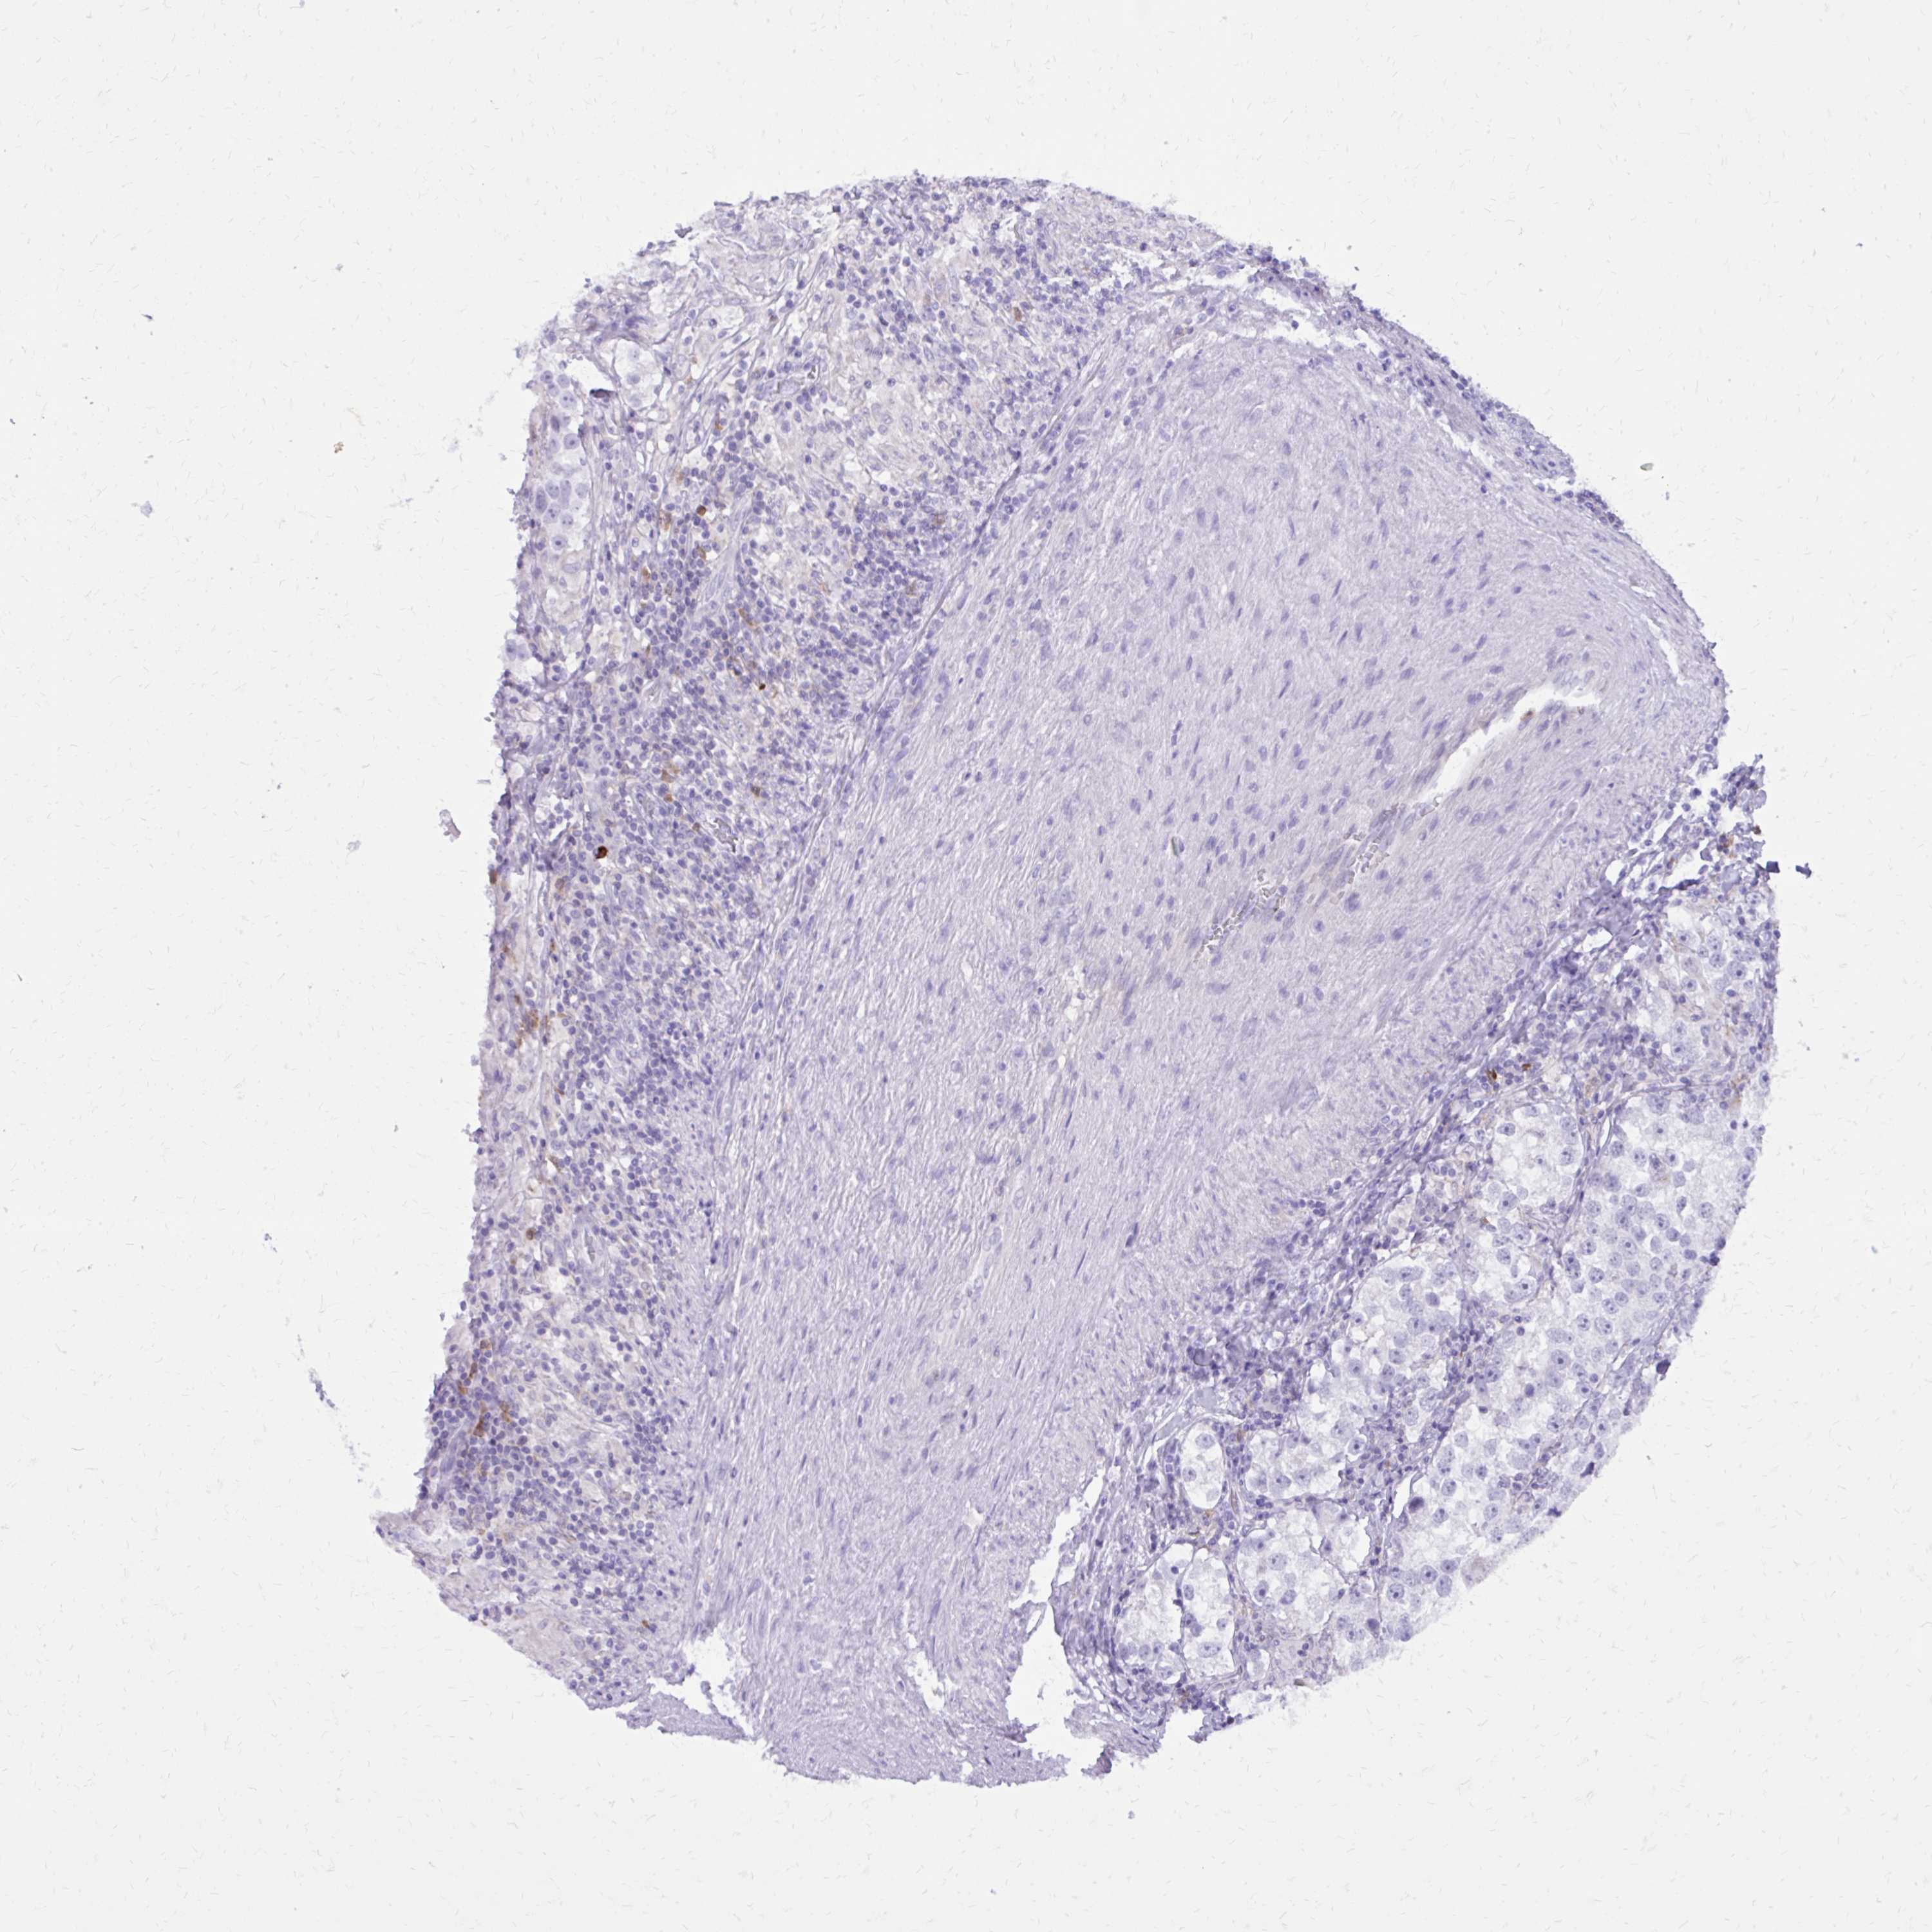

TESTIS CANCER - Protein expressioni

A mouse-over function shows sample information and annotation data. Click on an image to view it in a full screen mode. Samples can be filtered based on level of antibody staining by selecting one or several of the following categories: high, medium, low and not detected. The assay and annotation is described here.

Note that samples used for immunohistochemistry by the Human Protein Atlas do not correspond to samples in the TCGA dataset.

Antibody stainingi

Antibody staining in the annotated cell types in the current human tissue is reported as not detected, low, medium, or high, based on conventional immunohistochemistry profiling in selected tissues. This score is based on the combination of the staining intensity and fraction of stained cells.

Each image is clickable and will lead to virtual microscopy that enables deeper exploration of all samples and also displays staining intensity scores, fraction scores and subcellular localization as well as patient and tissue information for each sample.

Antibody HPA051282

Antibody HPA055838

Antibody CAB001515

Seminoma, NOS

Carcinoma, Embryonal, NOS

Teratoma, malignant, NOS